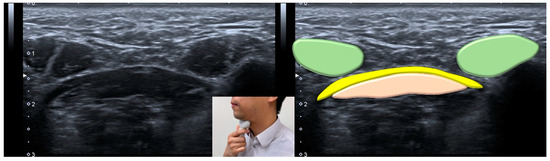

- Ogawa, N.; Mori, T.; Fujishima, I.; Wakabayashi, H.; Itoda, M.; Kunieda, K.; Shigematsu, T.; Nishioka, S.; Tohara, H.; Yamada, M.; et al. Ultrasonography to Measure Swallowing Muscle Mass and Quality in Older Patients With Sarcopenic Dysphagia. J. Am. Med. Dir. Assoc. 2018, 19, 516–522. [Google Scholar] [CrossRef]

- Gervasio, A.; D’Orta, G.; Mujahed, I.; Biasio, A. Sonographic anatomy of the neck: The suprahyoid region. J. Ultrasound 2011, 14, 130–135. [Google Scholar] [CrossRef]

- Mori, T.; Wakabayashi, H.; Ogawa, N.; Fujishima, I.; Oshima, F.; Itoda, M.; Kunieda, K.; Shigematsu, T.; Nishioka, S.; Tohara, H.; et al. The Mass of Geniohyoid Muscle Is Associated with Maximum Tongue Pressure and Tongue Area in Patients with Sarcopenic Dysphagia. J. Nutr. Health Aging 2021, 25, 356–360. [Google Scholar] [CrossRef] [PubMed]

- Ogawa, N.; Wakabayashi, H.; Mori, T.; Fujishima, I.; Oshima, F.; Itoda, M.; Kunieda, K.; Shigematsu, T.; Nishioka, S.; Tohara, H.; et al. Digastric muscle mass and intensity in older patients with sarcopenic dysphagia by ultrasonography. Geriatr. Gerontol. Int. 2021, 21, 14–19. [Google Scholar] [CrossRef] [PubMed]

| Ultrasonography | <1536 mm2 for the cross-sectional area of the tongue muscle <75.1 mm2 for the cross-sectional area of the digastric muscle |